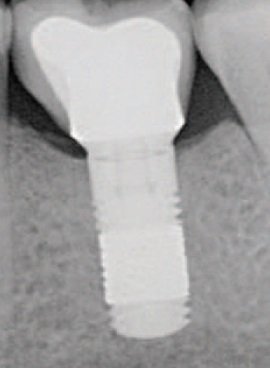

Aurea NP 3.5 mm – Phibo

País de Origen: España Conexión: Hexalobular con cono. Tamaño Plataforma: 3.2 mm plataforma. Tamaño total 3.5 mm. Tipo de cuello: 0.18 mm bisel mecanizado. Altura microespiras 0.3 mm. Peculiaridades de la Espira: Implante autoroscante. Espira mixta. Tamaño [...]